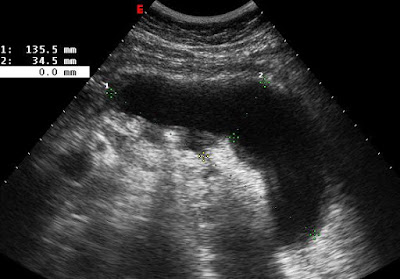

2 héttel később látott pseudocysta

2011.01.20. UH